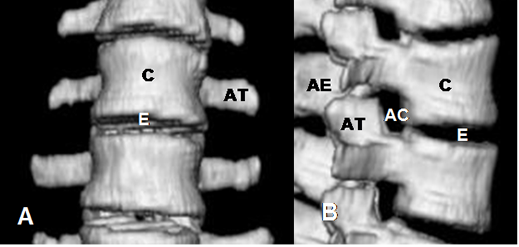

Fig 9. Columna lumbar normal.

A y B: TAC reconstrucciones 3D. E: Espacio intervertebral. C: Cuerpo, AT: Apófisis transversa. AE: Apófisis espinosa. AC: Agujero de conjunción.